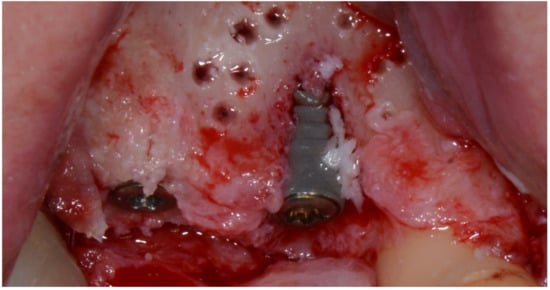

At second stage surgery, a mini-flap was prepared in order to connect healing abutment and protect the papilla; the bone lamina was still in place and it was necessary to drill through it in order to access the implant’s heads (Figure 17 and Figure 18).

Figure 17.

The bone lamina integrated.

Figure 18.

Progression of the case.

More than 3 mm of bone had formed above the implant heads and adjacent to the teeth, and the presence of the interdental papilla after the soft tissue had been conditioned shows proof of it (Figure 19).